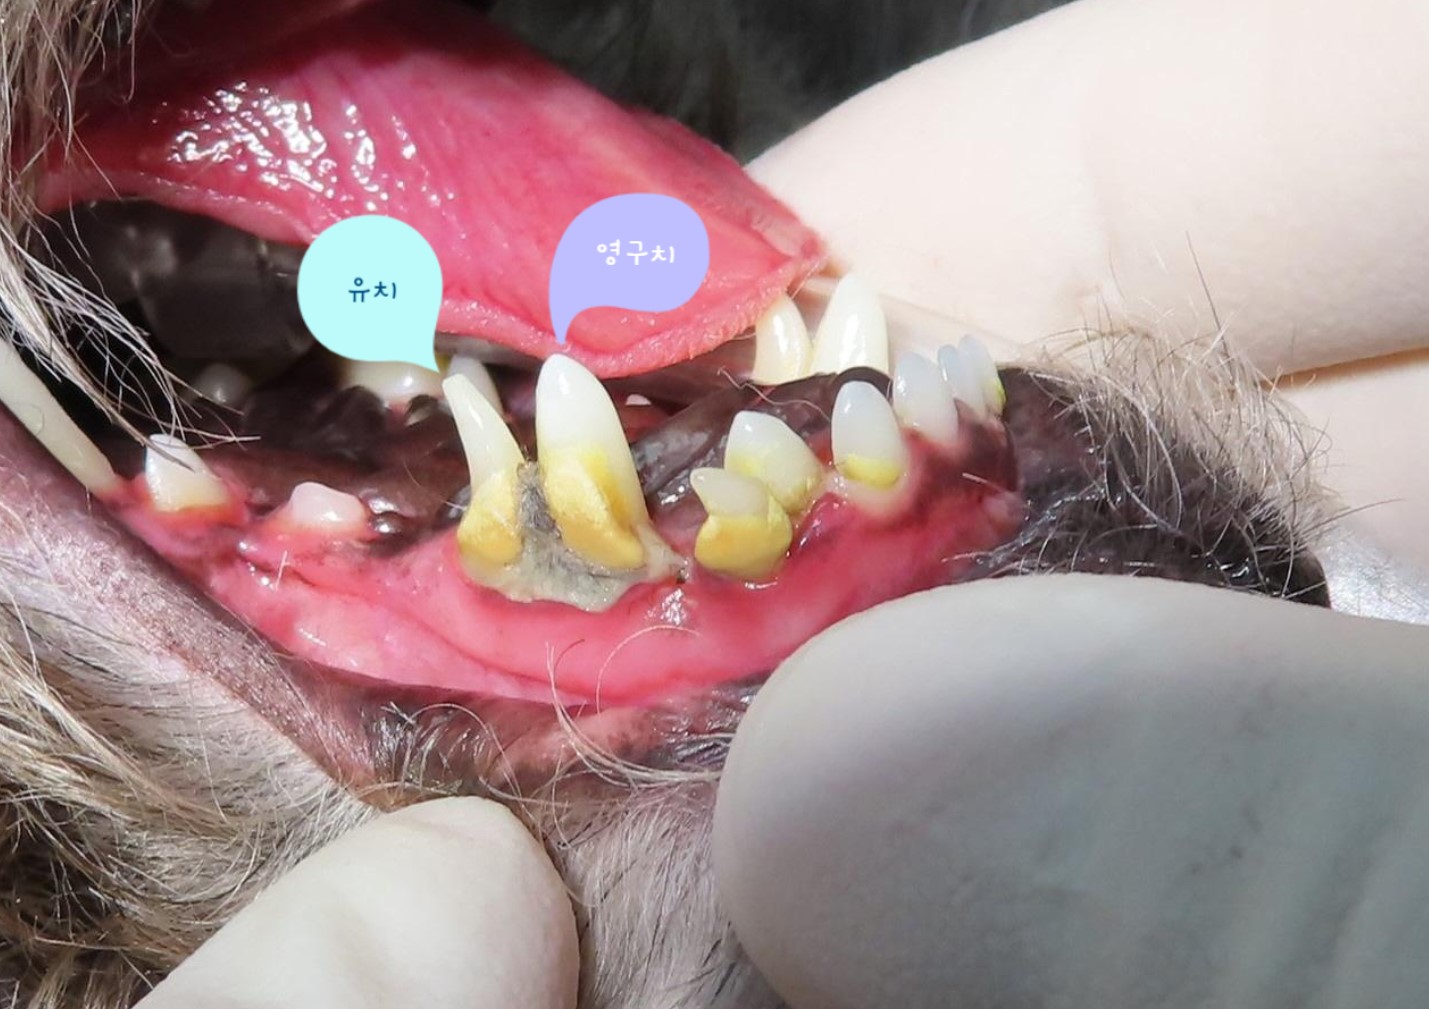

잔존 유치가 탈락되지 않아 영구치가 치아 사이에 같혀 있음 위 사진은 유치가 제때 탈락되지 않아 영구치가 세 번째 앞니 아래에 갇혀 있는 것을 보여줍니다.

세 번째 앞니도 송곳니 간섭으로 인해 정상위치 보다 위쪽으로 벗어나 있는 것(deviation)을 확인할 수 있습니다.

잔존 유치를 제거해 주었더니 별다른 교정 장치를 사용하지 않았음에도 2주 후 제위치로 이동하고 있는 송곳니를 확인할 수 있습니다.